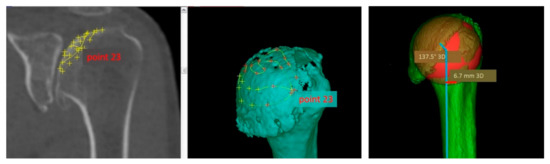

2.4. Radiological Analysis